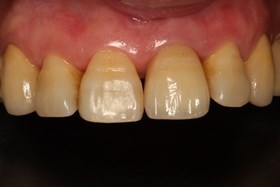

- 治療前全口X光片、口內正面照片。

治療前全口X光片、口內正面照片